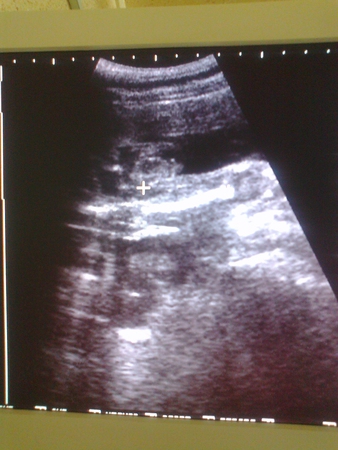

Так интересно!!! Если бы не прочитала ниже, ничего бы не разобрала)))) Хотя, у нас похоже в консультации врачи тоже не особо разбираются.... На 22 неделе с дуру решила сделать УЗИ у нас и услышала, что скорее всего мальчик, но 100% гарантии она не даст - просто ей так кажется .... Прикольно!

и она права-очень много случаев в практике,когда яички не опустились и показывает девочку до рождения,а иногда поставит кулачок между ножками и уже мальчиком делается.А есть такие ,которые ножки до самого рождения не открывают.Родители бегают по врачам,чтоб пол узнать,а оно уперлось и не показывает.Лучше всего пол ребенка видно с 18 до 28 недели.Потом размеры ребеночка увеличиваются,это все сжимается в кучку маткой и попробуй разглядеть

Понятно )))) Я специально конечно не задавалась целью узнать пол, но на 12 недельке делали УЗИ в перинатальном центре и тогда врач сказала что 100% девочка. В общем, на этой недельке наверное узнаем кто там прячется точно )))))